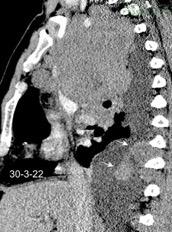

Marzo 2014: Perforación longitudinal distal secundaria a episodio de vómito (síndrome de Boerhaave). Derrame pleural izdo. que evoluciona a empiema.

Wang C-T et al. Tension hydropneumothorax in a Boerhaave syndrome patient: A case report . World J Emerg Med, 2021. Katabathina V et al. Nonvascular, nontraumatic mediastinal emergencies in adults:a comprehensive review of imaging findings. Radiographics. 2011.